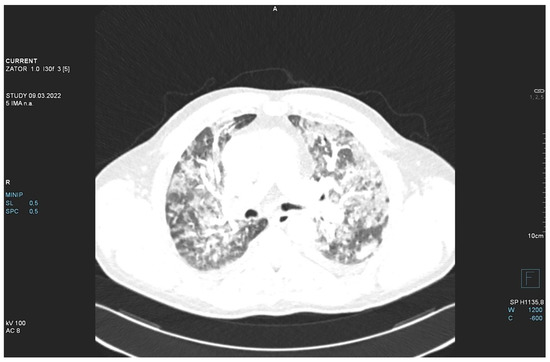

On day 3, the patient developed dyspnea, with bilateral rales and crackles over the lungs. On the chest X-ray, numerous signs of bilateral heterogenous shading with unclear etiology were observed (Figure 1).

Figure 1.

Chest X-ray. L—left side.

The patient required oxygen therapy, and initially, due to a lack of diagnosis, he received empirically broad-spectrum antibiotics (meropenem, linezolide). On laboratory testing, a further increase in inflammatory and coagulation biomarkers (CRP, ferritin, interleukin-6, D-Dimer, fibrinogen) was observed. Blood cultures as well as a respiratory PCR multitest were negative. Due to the dynamic increase in D-dimers and the elevation of cardiac biomarkers (BNP, NT-proBNP) along with dyspnea, an angio-CT was performed. It excluded pulmonary embolism, but it revealed widening of the pulmonary trunk and pulmonary arteries, as well as alveolar compaction in both lungs and bilateral pleural effusion. Pulmonary edema was diagnosed (Figure 2, Figure 3 and Figure 4).